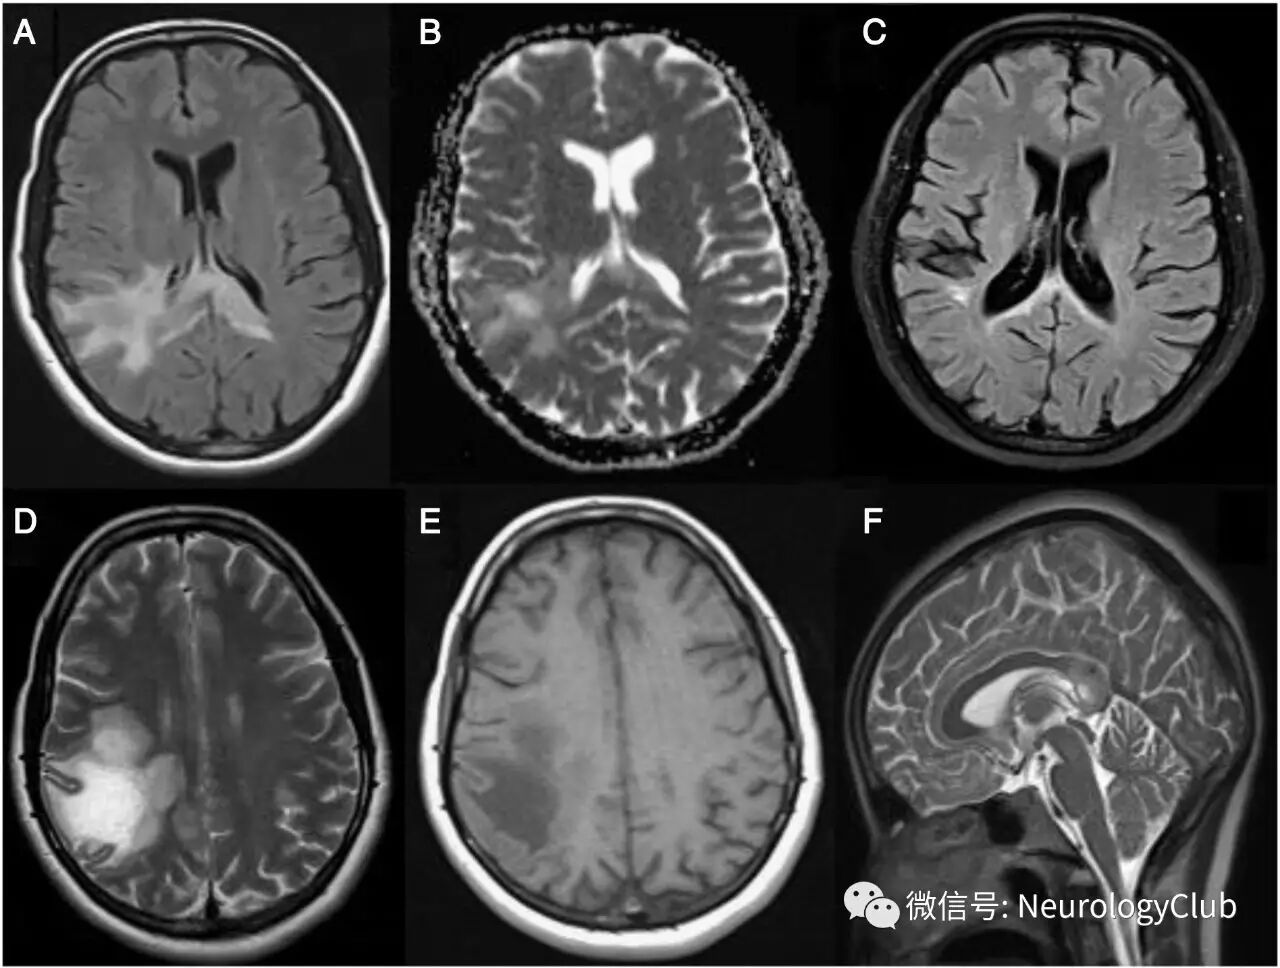

31岁左利手女性,既往体健,怀孕12周时出现快速进行性言语困难,左侧肢体无力,左侧部分运动性癫痫发作以及全头部疼痛,病程超过15天。入院查体,患者无发热,神志清,经皮质运动性失语,构音障碍和左侧轻偏瘫。头颅MRI提示右侧额顶叶较大病灶,累及胼胝体压部,左顶叶皮质下一小病灶(图)。脑血管造影正常。

(图:FLAIR[A],T2WI[D]和T1WI[E]可见额顶叶较大的皮质-皮质下病灶伴坏死,累及胼胝体压部;病灶在ADC上呈高信号[B];矢状位FLAIR[F]可见肿瘤样病灶位于胼胝体压部;12月后复查FLAIR[C]可见脑萎缩伴残留的额顶叶和胼胝体高信号)

12月后随访MRI提示脑萎缩以及残留的额顶叶和胼胝体病灶(图)。